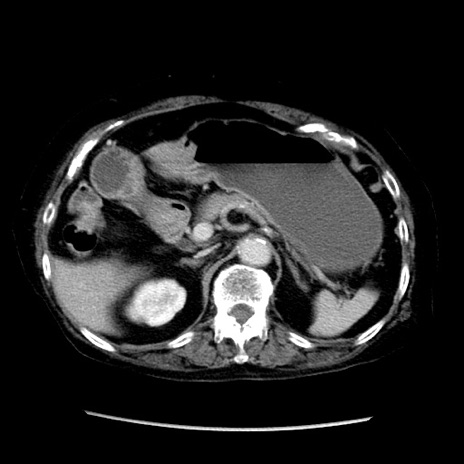

症例14(横断像)

【症例】 90歳代女性

【主訴】 腹痛・嘔吐

【現病歴】今朝から左側腹部痛を認めた。 経過観察していたが、嘔吐を認めたため来院。

【既往歴】 子宮癌術後

【身体所見】 意識清明、BP 127/54mmHg、P 98bpm Sp02 95%(RA)、BT 35.8°C、腹部平坦・軟腸ぜん動音聴取良好、右下腹部圧痛(+) 反跳痛なし

【データ】WBC 9800、CRP 0.46